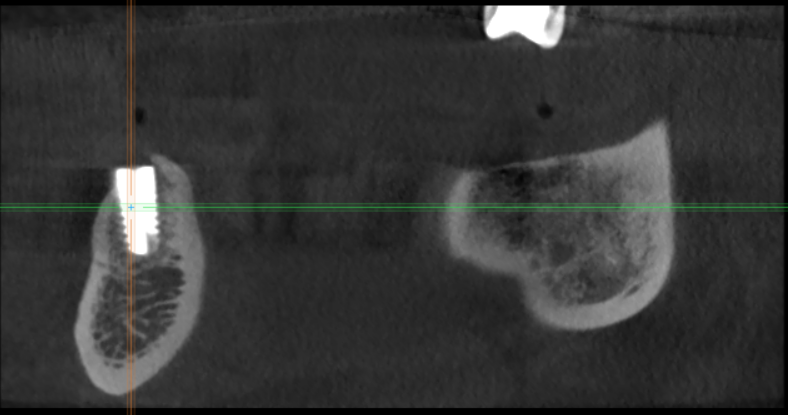

m-art-a23 Опубликовано 21 апреля, 2021 Поделиться Опубликовано 21 апреля, 2021 Здравствуйте. Два дня назад мужу установили 5 имплантов Ankylos на нижнюю челюсть (2+3). Спустя 30-40 мин после операции появилась сильная острая боль, которая не уменьшается по настоящее время. Боль похожа по ощущениям на пульпитную, не снимается никакими НПВС, кроме кеторолака. А/б, А/гистаминные, холод местно, хлоргексидин - все рекомендации выполнялись. На осмотре врачом не обнаружено следов воспаления, КТ сделал - без особенностей. Что может служить причиной такой боли, сколько она может длиться и что делать в данной ситуации? Врач-имплантолог ничего внятного не предложил. Ссылка на КТhttps://cloud.mail.ru/public/EvKn/ULqxLy6BD Ссылка на комментарий

red_butler Опубликовано 22 апреля, 2021 Поделиться Опубликовано 22 апреля, 2021 7 минут назад, m-art-a23 сказал: Нет, не один. Но он лучший. Скажите пожалуйста, что служит причиной боли, по-Вашему? Неужели все импланты нужно убирать только по Кт трудно судить, но есть вопросы по позиционированию имплантов... боль может быть вызвана перегревом кости во время формирования ложа импланта, но в этом случае она появляется примерно с третьего дня. Так же боль может вызывать гиперкомпрессия импланта, и может болеть кость если ее придавили формирователем десны. Я бы обсудил с хирургом удаление среднего импланта слева 1 Ссылка на комментарий

Irouil Опубликовано 22 апреля, 2021 Поделиться Опубликовано 22 апреля, 2021 (изменено) 1 час назад, m-art-a23 сказал: Благогдарю за совет. Если Вам не трудно, объясните пожалуйста, что не так со средним имплантом. Описанные процессы, если таковые имеют место быть, должны постепенно прийти в норму? Другими словами, сколько еще нужно времени, чтобы окончательно принять решение об удалении импланта (имплантов)? Сегодня третьи сутки после установки. Боль сохраняется. Средний имплант расположен чрезвычайно близко к соседнему, расположенному кпереди от него. С очень большой долей вероятности это может привести к значительной резорбции (убыли) костной ткани между ними, что для любых имплантов очень вредно, а для конкретно Анкилосов - губительно из-за особенностей их протезирования. Если неблаготворные процессы (компрессионный или термический некроз) присутствуют, то импланты просто не интегрируются (не приживутся) - те, что зашиты не выдержат нагрузки при раскрытии, а тот, на котором стоит ФДМ - расшатается через 2-3 недели. Это не призыв проверять его стабильность языком, сейчас его лишний раз лучше не трогать. В норме после имплантации боли держатся 1-2 дня, если все не очень хорошо - держатся 2-3 недели, но даже в таком случае имплант может интегрироваться, поэтому решение об его удалении в таком случае должно, по моему убеждению, быть совместным между врачом и пациентом, и приниматься в индивидуальном порядке Изменено 22 апреля, 2021 пользователем Irouil Ссылка на комментарий